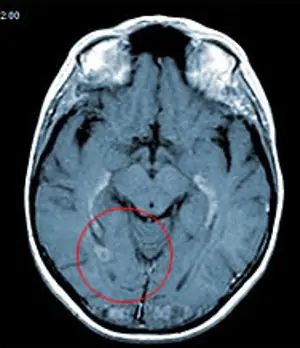

Лечение метастазов рака легкого в головном мозгу кибер-ножом

МРТ-изображение с двумя метастазами рака легкого в головной мозг

Оба метастаза были удалены за один сеанс, длительностью 1 час. На снимке результат контрольного обследования через 4 месяца после лечения. Обе опухоли были удалены, после лечения пациент в тот же день вернулся к работе